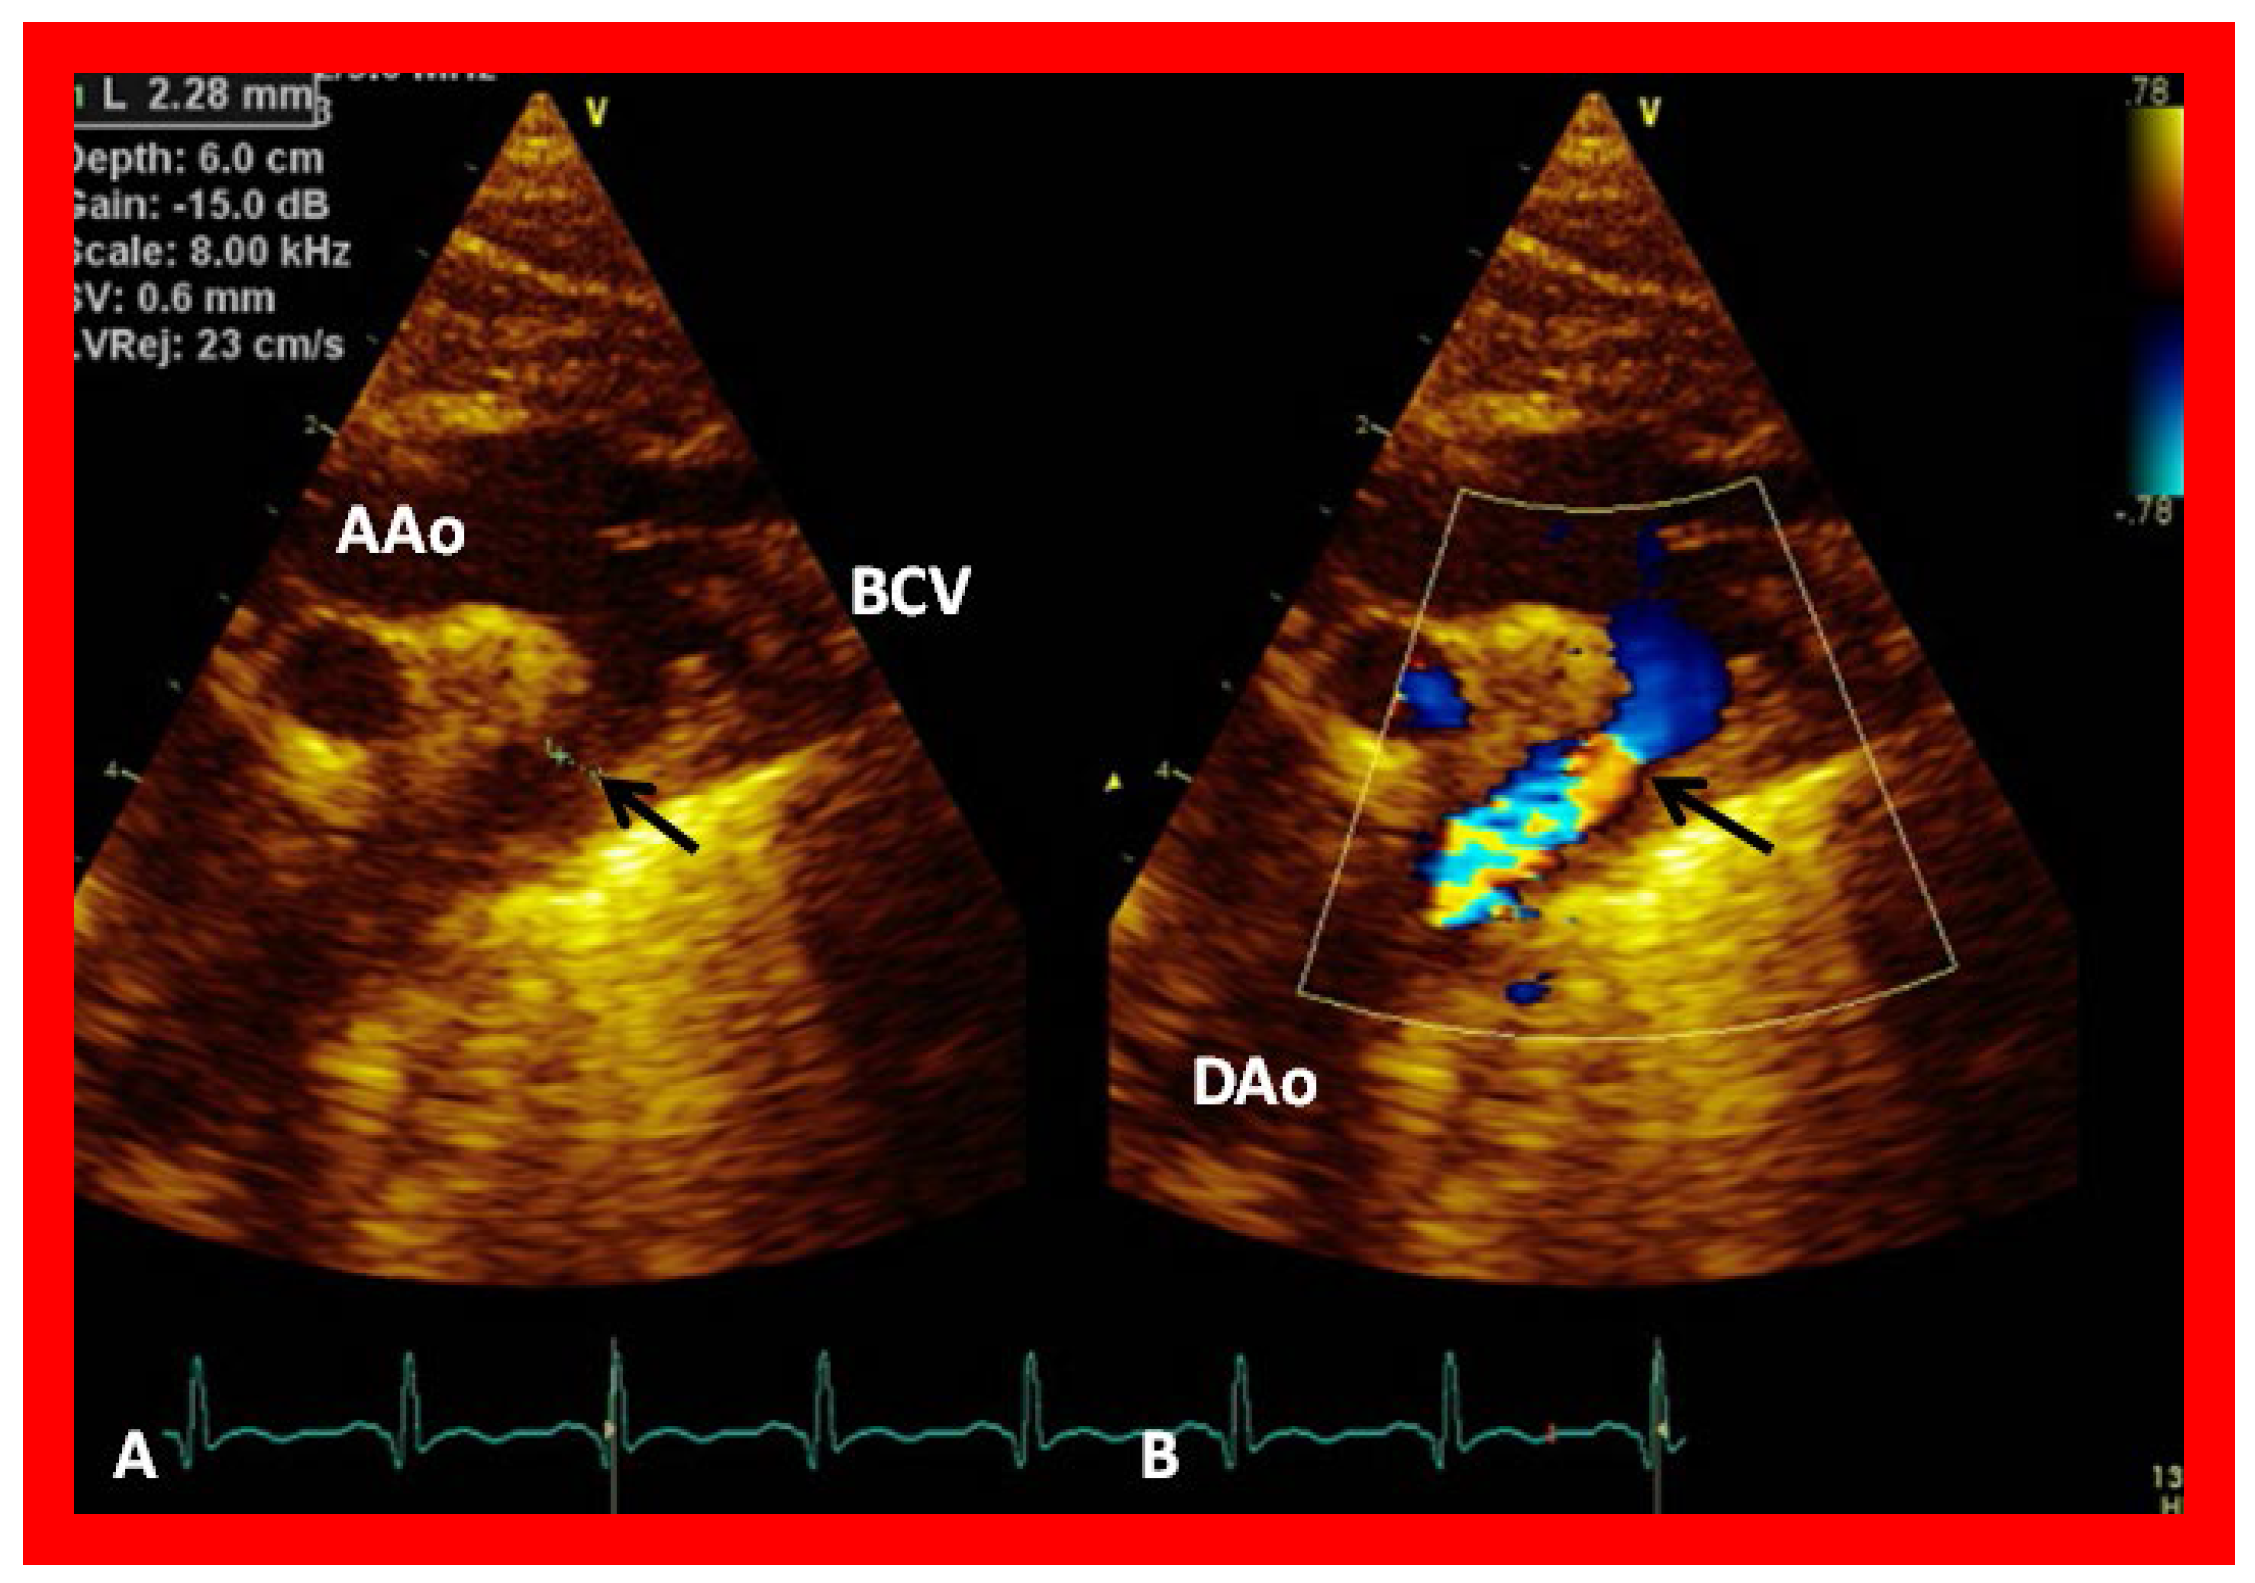

Figure 32. (A) Suprasternal notch view of the aortic arch (Arch) in a patient with aortic coarctation (arrow) in 2D (A) and color flow mapping (B), demonstrating turbulence at the site of coarctation (arrow). AAo, ascending aorta; BCV, brachiocephalic vessels; DAo, descending aorta. Reproduced from Reference [53].

Coarctation of the aorta is particularly common in Type II (transposition of the great arteries) patients; if present, it is usually dealt with at the time of initial palliation in the neonatal period. It is possible that coarctation was missed at the time of initial presentation or it may have developed subsequently. Alternatively, recoarctation may have developed following prior surgery or balloon angioplasty. Echo studies should be scrutinized to demonstrate the patency of the descending aorta (Figure 31) and, if coarctation is demonstrated (Figure 32; Figure 33), it should be treated either by balloon angioplasty or surgery, as deemed appropriate [38].